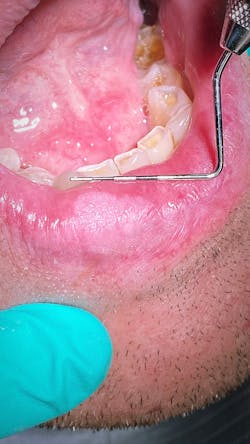

In less than five minutes, I whipped out my iPhone, snapped a picture, showed it to the patient, emailed it to my front desk to drop in the patient’s chart, texted it to my oral surgeon colleague for his thoughts, and dismissed the patient with instructions to see him back in two to three weeks. Done and done.

What are your differentials? I’ve got mine. If you can’t give me at least three, then let’s get your path skills up to speed. This is the place to do just that.

Here are my take-home points. Maximization of available resources. Don’t hesitate to take action on things that look harmless or nonpathological. And last but not least…keep it simple. I can’t make it any simpler than that!